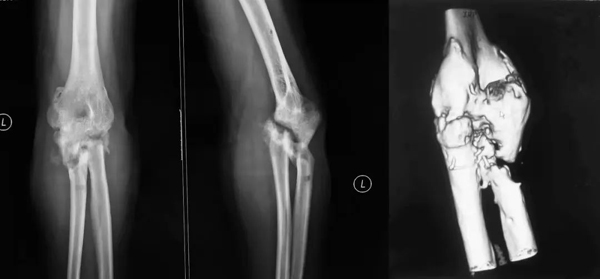

患者是福建省的一名27岁的年轻男性,2年半前工作时不慎摔倒在路边水沟里,造成了严重的开放肘关节骨折脱位。在当地先后进行了五次手术后,肘关节肱尺关节完全骨性融合,软骨缺失,桡骨头已切除,上尺桡融合,尺骨近端不愈合,形成假关节微动,前臂旋转功能完全受限(图1)。伤痕累累的胳膊,疼痛、无力、活动受限,使患者的工作和生活受到了极大的影响,十分痛苦。

图1:男,27岁,术前X片及三维CT:肱尺关节骨性融合,上尺桡融合,桡骨头切除术后,尺骨近端不愈合假关节形成。